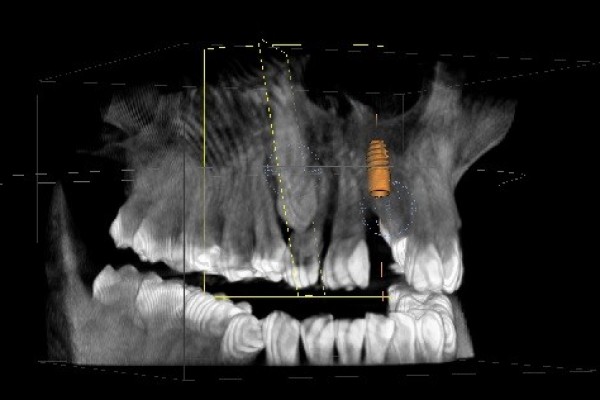

Mit der Digitalen Volumentomographie (DVT) bieten wir unseren Patienten ein hochmodernes dreidimensionales Diagnoseverfahren, welches eine deutlich besseren Bildqualität, erhöhte Sicherheit für Patient und Behandler sowie eine geringere Strahlendosis als bei einer herkömmlichen CT bedeutet .

Die DVT arbeitet mit Röntgenstrahlen. Wie auch die Computertomographie (CT) können mit der DVT hochauflösende Schnittbilder erstellt werden, diese haben jedoch eine deutlich bessere Auflösung. Hierdurch ist eine noch genauere Diagnose und spätere Therapie möglich.

Die Röntgenröhre produziert zweidimensionale Einzelaufnahmen, die von einem Hochleistungsrechner zu einem dreidimensionalen Datensatz umgerechnet werden.

Innerhalb kürzester Zeit wird so direkt eine präzise Diagnosegrundlage erstellt, der wir alle Informationen entnehmen können, die wir für Ihre Therapieplanung benötigen.

• Implantatplanung in der 3D Simulation

• exakte Positionierung von Implantaten

• Einschätzung des Knochenangebots und der Knochenbeschaffenheit vor der Implantatversorgung